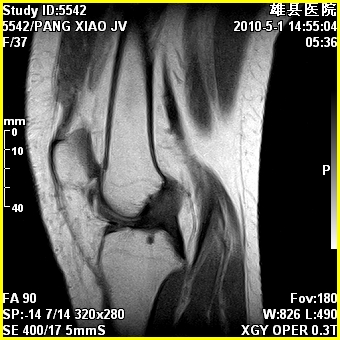

标题: MRI2894:患者右膝关节疼痛两月余,无明显外伤史 [打印本页]

标题: MRI2894:患者右膝关节疼痛两月余,无明显外伤史

右股骨下端前内侧类圆形异常信号,位于干骺端,呈长t1长t2改变,但信号不均,t1图上病灶中心见小片状稍高信号影,t2图上见散在稍低信号影,stir像呈高信号,因病灶较小,缺乏特征性改变,结合患者年龄及部位,考虑嗜酸性肉芽肿可能性大。胫骨关节面下的小囊状异常信号,如果一元论考虑则为嗜酸性肉芽肿,不过发生在这个部位的少见,二元论考虑为邻关节骨囊肿。半月板与前后交叉韧带均未见异常。

右股骨下端前内侧干骺端囊性良性病变,考虑 1内生软骨瘤 2骨囊肿 3肉芽肿。